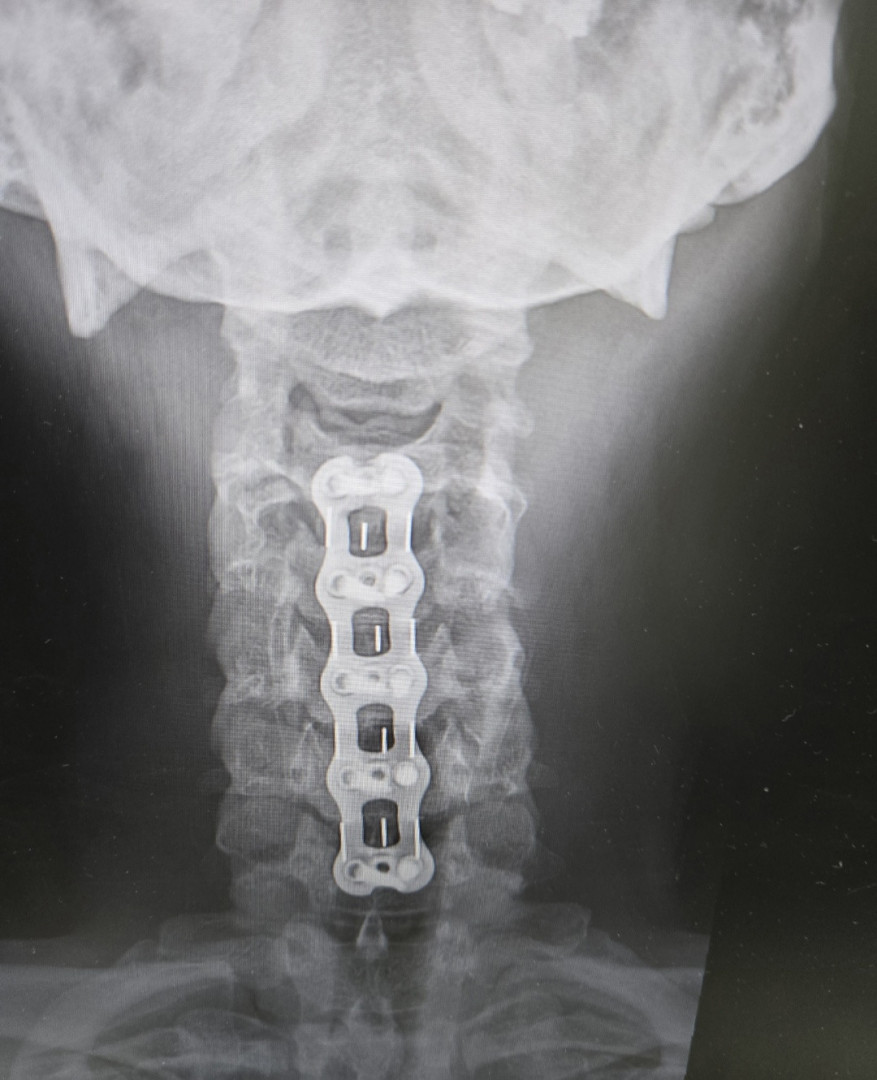

I made a massive comeback after being medically retired and having my 11th knee surgery, a 5 lvl neck fusion, 5 TBIs, and a broken hip.

Being able to climb a set of bleachers in 10 more years to watch my kids play sports. As well as keeping the pain at bay. With my long list of injuries from the military, Im in less daily pain, the more fit I am. Ive had 7 (L) knees scopes, 4 (R) Knee scopes, a broken (L) hip, torn Bursa and Labrum, 4 bulged lumbar, 5 level neck fusion and 5 Traumatic Brain Injuries. God, my kids and the Gym keep me going. My starting weight was 275lbs, im now 203 and 16.4%bf. Wouldn't be here without God.